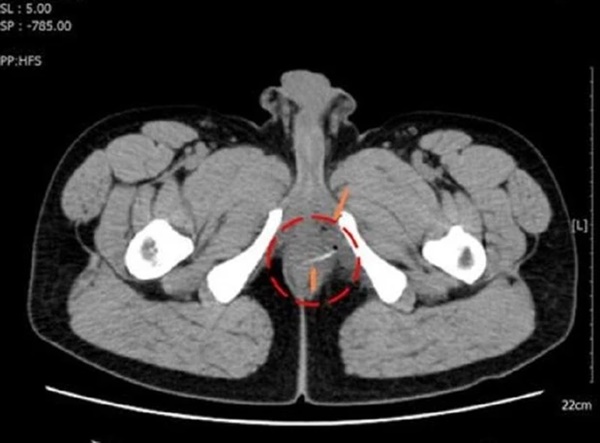

Bệnh nhân được chụp CT-Scan truy tìm nguyên nhân gây đau bất thường ở vùng hậu môn

Trên hình ảnh kiểm tra, bác sĩ phát hiện vùng đại tràng của bệnh nhân có dị vật cản quang hình que kèm bóng khí. Bệnh nhân đã được chỉ định nhập viện phẫu thuật.

Hình ảnh kiểm tra phát hiện chiếc xương cá cản quang ở vị trí trực tràng của bệnh nhân

Trong quá trình mổ, ê kíp phát hiện chiếc xương cá dài khoảng 3cm nằm ở vùng trực tràng, đâm thủng thành ruột và tạo áp xe nhưng may mắn chưa gặp biến chứng nguy hiểm. Các bác sĩ đã lấy dị vật ra khỏi cơ thể bệnh nhân và khâu lại vết thương. Sau phẫu thuật, sức khỏe của bệnh nhân đã bình phục tốt.